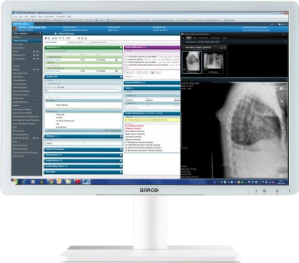

Kompaktne kirjeldav meditsiinimonitor on seade DICOM-standardile vastavate failide esitamiseks PACS-süsteemist, et tõlgendada meditsiinilisi kujutisi. Üldiselt on need diagnostilised monitorid, mis taasesitavad kõige täpsemal viisil igasuguste diagnostikaseadmete kujutiste üksikasju. Need on nii ühevärvilised kui ka värvilised meditsiinilised monitorid maatriksitega 1 MP kuni 5 MP, ühe või kahe monitori konfiguratsioonis ja 4 MP, 6 MP, 8 MP, 12 MP ühe paneeli konfiguratsioonis. Viimastel aastatel oleme näinud tugevat suundumust monokroomsete monitoride asendamisel värviliste monitoridega, mis võimaldavad kuvada pilte paljudest erinevatest viisidest, samuti traditsiooniliste kahe monitoriga jaamade asendamist ühe meditsiinilise monitoriga, millel on kõrge (ekvivalentne) eraldusvõime, mis tagab kõrgeim pildikvaliteet vastavalt DICOM standardile.

Olles teadlik, et kirjeldavad monitorid (kogu kirjeldavad jaamad) on diagnostikaprotsessi kriitiliseks lüliks, varustavad tootjad monitore mitmete lisafunktsioonidega, mis reguleerivad ja korrigeerivad automaatselt pildiparameetreid. See annab kindlustunde õiges diagnoosis ja vabastab radioloogid vajadusest teostada pidevat seadmete kontrollimist. DICOM standardile vastav meditsiiniline monitor võimaldab õigeks diagnoosimiseks vajaliku pildi täpset kuvamist, tagades samas ühilduvuse teiste seadmetega.

Hoolimata mitte eriti nõudlikest nõuetest CT- ja angiograafiamonitoride kujutise parameetritele, pakuvad meditsiiniseadmete tootjad palju arenenumaid lahendusi, mis võimaldavad palju detailsemat pildianalüüsi, kiiremat diagnoosimist ja paremat töömugavust. See on kooskõlas ka suundumusega kasutada monitore paljude erinevate meetodite uuringute kirjeldamiseks. Kavandatavate monitoride diagonaali suurus on 21,5-27 tolli ja eraldusvõime 2 MPix kuni 8 MPix. Nad suudavad kuvada nii värvilisi kui ka ühevärvilisi pilte, mis vastavad DICOMi osale 14. Mõnel neist on sisseehitatud spetsiaalsed andurid, mis kontrollivad automaatselt pildiparameetreid. See tagab õige pildi kuvamise ja täpse diagnoosi.

Spetsiaalsed diagnostikajaamad

Meie pakkumisest leiate ka täielikult konfigureeritud diagnostikajaamad igat tüüpi testide jaoks. Jaamade baasil töötavad kaks varianti, millest esimene on 10. põlvkonna Intel® Core™ i5 protsessoritega, teine XEON E-2224G 1P 4C/4T protsessoriga. Standardne töömälu on 16 GB. Salvestusruumiks on kaks SSD-d, mis töötavad RAID 1 konfiguratsioonis (peegeldades), tagades täieliku andmeturbe. Kui diagnostilisi pilte kavatsetakse ajutiselt jaama salvestada, on jaam lisaks varustatud 2TB või suurema HDD-ga. Iga jaam on varustatud spetsiaalse meditsiinilise graafikakaardiga, mis on üks ülalloetletutest. Süsteemi on installitud monitori kalibreerimis- ja juhtimistarkvara.

Kogu süsteem töötab Windows 10 Pro operatsioonisüsteemi kontrolli all. Jaamad on varustatud avariitoitesüsteemiga UPS.